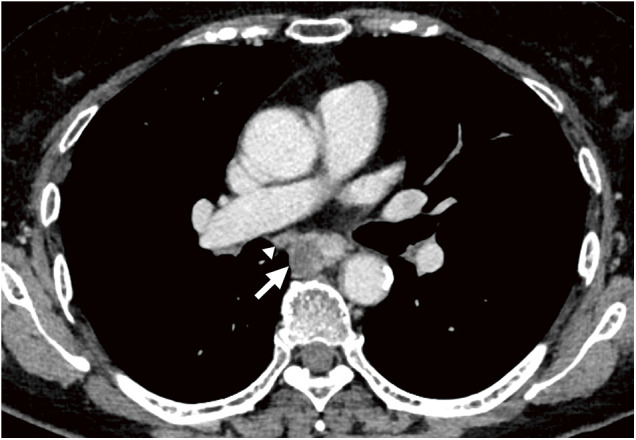

一名68岁女性被诊断为临床T3N1M0中胸食管癌。术前三维计算机断层扫描显示右上后肺静脉(RSPPV)异常,位于右中间支气管后方。患者行胸腔镜食管切除术并纵膈淋巴结清扫术。在我们开始解剖右侧隆突下淋巴结之前,我们静脉注射吲哚菁绿以确定异常RSPPV的运行位置,我们能够准确地确定其位置,正确识别血管和周围组织之间的差异。尽管患者在异常血管附近有淋巴结转移,并且由于粘连紧密,剥离手术很困难,但术中荧光成像使我们能够在没有任何多余血管损伤的情况下进行剥离。在这种情况下,术中荧光成像非常有用,可以提供关于异常位置的准确术中信息,促进更安全的手术。

A 68-year-old woman was diagnosed with clinical T3N1M0 middle thoracic esophageal cancer. Preoperative three-dimensional computed tomography indicated a right superior posterior pulmonary vein (RSPPV) anomaly, which ran behind the right intermediate bronchus. The patient underwent thoracoscopic esophagectomy with mediastinal lymph node (LN) dissection. Before we began the dissection of the right subcarinal LN, we administered indocyanine green intravenously to confirm the running position of the anomalous RSPPV, and we were able to ascertain its placement accurately with correct recognition of the difference between the blood vessels and surrounding tissue. Although the patient had LN metastasis adjacent to this anomalous vessel and the dissection procedure was tough due to tightly adhesion, intraoperative fluorescent imaging enabled us to perform the dissection without any superfluous vascular injury. Intraoperative fluorescent imaging is very useful in such cases, providing accurate intraoperative information on the location of the anomaly and facilitating safer surgery.